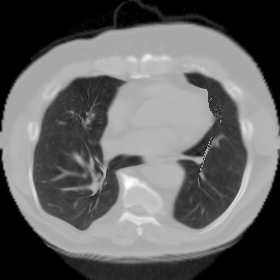

7.3. Real CT images

We now consider applying the proposed image registration method on real lung CT images retrieved from the National Lung Screening Trial (NLST) dataset [1]. Fig. 9(a) and Fig. 9(b) show two slices of lung CT images that we use as the source and the target (see Fig. 9(c) for the absolute intensity difference). We remark that the CT images are originally with different intensity, and so we apply an intensity histogram matching before running the registration experiment. Fig. 9(d) shows the registration result obtained by our proposed method. It can be observed that our method successfully produces a large deformation on the right lung of the source image to match that of the target image (see also Fig. 9(e) for the final absolute intensity difference). On the contrary, DDemons [47] (Fig. 9(f)), LDDMM [5] (Fig. 9(g)), Elastix [29] (Fig. 9(h)) and DROP [18] (Fig. 9(i)) all fail to produce an accurate and bijective registration result. This shows that our method is more capable of handling large deformation image registration.

We then test our method on slices of chest CT images obtained from the Open Access Biomedical Image Search Engine [2]. Fig. 10(a) and 10(b) show the source image and target image respectively, and the intensity difference is shown in Fig. 10(c). The registration result obtained by our proposed method is shown in Fig. 10(d) (see also the result with the deformed underlying grid in Fig. 10(e)). From the final intensity difference plot in Fig. 10(f), it is easily to see that our method matches not only the two large components but also the small dot at the center very well. On the contrary, DDemons [47] produces a suboptimal registration result with a significantly larger mismatch of the small component at the center (see Fig. 10(g) and Fig. 10(h)).